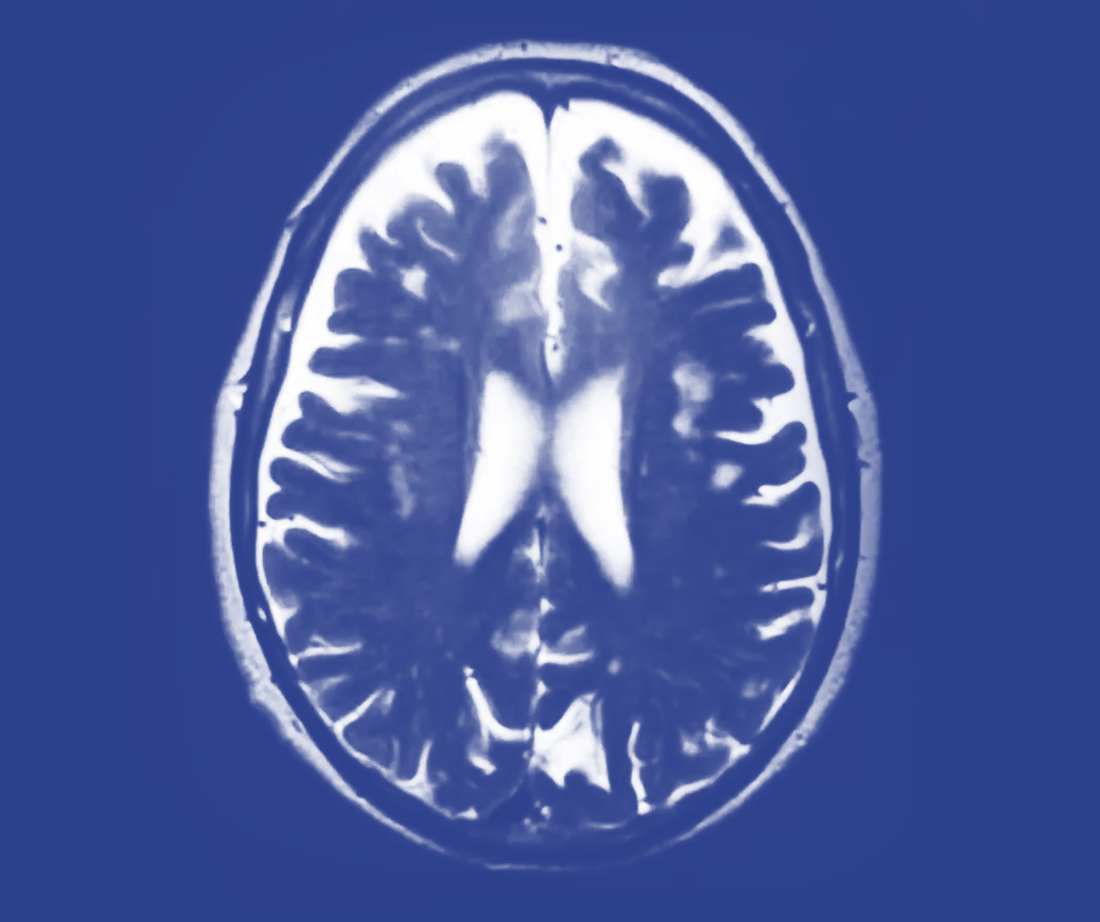

How are brain tumours diagnosed?

Suspicious symptoms should be investigated with a CT scan of the head. This will demonstrate a brain tumour, however an MRI scan will be needed to further delineate the margins of the tumour and also to create a treatment plan for each individual. Occasionally an angiogram will be required pre-operatively to identify the blood supply of tumours and obliteration of this blood supply may be performed to minimise the risks of surgery.